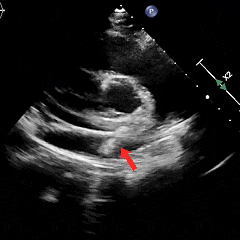

左右盘面展开

左盘展开,轻轻牵拉成型线辅助左盘成型,后撤钢缆和鞘管使左盘贴靠房间隔

后撤鞘管,展开右盘面,钢缆轻轻前推使其贴靠房间隔